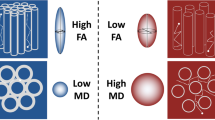

Quantitative assessment of DTI is feasible by calculating multiple parameters as apparent diffusion coefficient (ADC) that reflects molecular diffusivity under restriction and fractional anisotropy (FA) as a quantitative index used to characterise directional variability in diffusion Figs. 1 and 2.